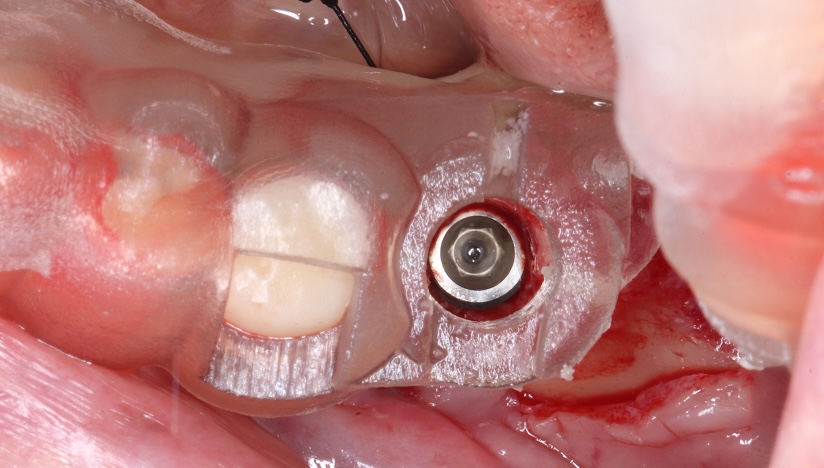

切開をせずに

インプラントをした症例

主訴

前歯がグラグラしてきた

診断

臼歯部支持の喪失に伴う前歯部への過大な咬合負担

および上顎洞底の高度な歯槽骨吸収

治療方針

前歯部の動揺は、臼歯部での垂直的な咬合支持の欠如により、前歯部へ過大な負担が集中していることが原因と考えられた。

臼歯部には既存補綴装置が装着されていたが、十分な咬合支持が得られていなかったため、インプラントによる咬合再構築を計画した。

また、上顎洞底の骨吸収が高度であったため、インプラント埋入に先立ち両側サイナスリフトを行い、十分な骨量を確保した上でインプラント埋入を行う方針とした。

患者は外科的侵襲に対する不安が強かったため、最終的にはフラップレスでのインプラント埋入を計画した。

治療内容

両側サイナスリフト

フラップレスインプラント埋入(4本)

治療期間

約6〜8ヶ月(骨成熟期間を含む)

治療費用

1,600,000

結果

十分な骨造成が得られ、フラップレスによる低侵襲なインプラント埋入が可能となった。術後経過も良好で、咬合支持の再構築による機能回復が得られている。

治療の

リスク

シュナイダー膜の穿孔、上顎洞炎、骨量不足により追加処置が必要となる可能性

考察

高度な骨吸収症例では、インプラント埋入と同時に骨造成を行う方法も選択肢となる。 本症例では骨量の確実な獲得と安全性を優先し、サイナスリフトを先行する段階的治療を選択した。

その結果、十分な骨量が確保され、最終的にフラップレスによる低侵襲なインプラント埋入が可能となった。外科的侵襲を可能な限り抑えながら、安全性と長期的安定性を両立した治療につながった症例である。